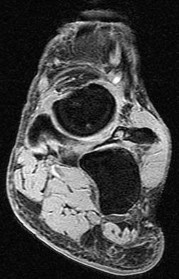

QUESTION 7

Figures 7a through 7h

1

Normal foot

2

Calcaneonavicular (CN) coalition

3

Talocalcaneal (TC) middle facet coalition

4

TC posterior facet coalition

Tarsal coalitions occur when primitive mesenchymal cells fail to differentiate and form the

normal articular separations between the tarsal bones of the hindfoot. Overall incidence is difficult to determine because many affected people are minimally symptomatic or asymptomatic. Symptomatic tarsal coalitions typically present in adolescents as a painful flatfoot; however, there are a number of possible presentations, and occasionally symptoms do not appear until adulthood. Most tarsal coalitions are between the calcaneus and the navicular (CN) and the talus and the calcaneus (TC). Although most TC coalitions are across the middle facet, posterior facet coalitions do occur. Plain radiographic evaluation of suspected tarsal coalition is the mainstay for diagnosis. However, coalitions can be bony or fibrous, and making the diagnosis can be difficult. The addition of CT images to distinguish bony definition and MR images to decipher soft tissue can aid in diagnostics. Bony coalitions appear as definite bony bridging between the bones, while fibrous coalitions are suspected when distortion of the bony anatomy is seen. Bony coalitions are best seen on the oblique view (CN) and Harris axial view (TC). There are a number of secondary signs such as the anteater (AE) sign (elongation of the anterior process of the calcaneus as it extends to the navicular as seen on the lateral view [CN]). talar beaking (traction spur of the talar neck thought to result from abnormal stresses as seen on the lateral view [both CN and TN]), and the “C” sign (a continuous cortical contour from the medial talus to the sustentaculum tali [ST]) as seen on the lateral view (TC). A number of newer signs are not as well known, such as a broad mediolateral dimension of the navicular on the anteroposterior (AP) view (the

navicular is wider than the talar head [CN]), nonvisualization of the middle facet on the lateral view (TC), the brick sign (a normal ST is flat, but a distorted ST is enlarged and curved [CN]), and a tapered lateral navicular bone as seen on the AP view (the medial navicular [CN] is much thicker than the lateral navicular).

Figure 7a shows a mild flatfoot with lateral peritalar subluxation of the navicular. Figure 7b does not show an open MF and has a questionable C sign. Figure 7c shows that the opening between the calcaneus and the navicular appears normal without distortion. Figures 7d, 7e, 7g, and 7h show a lateral sloping distorted middle facet consistent with a middle facet coalition, and Figure 7f shows a normal posterior facet.